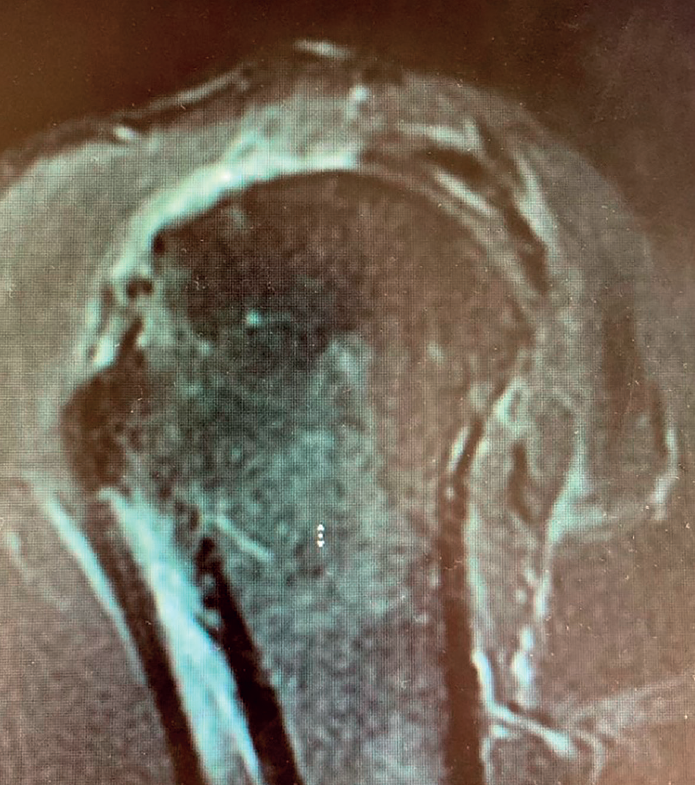

Boileau in 2005 or Simovitch in 2007(28,32) concluded that reverse replacement is unable to secure the restoration of external rotation. In many patients, only the teres minor will be able to afford active external rotation. If the teres minor presents rupture, retraction or adipose degeneration (which can be assessed by magnetic resonance imaging or computed tomography), we can predict a poorer outcome in these individuals, with an external rotation deficit(33,34). The lack of external rotation may prove quite disabling, especially in patients that use the arm in abduction. For this reason, some investigators such as Longo, in 2011(35), indicate the possibility of latissimus dorsi transfer to the reverse replacement implant, to restore external rotation in the patient.

Apart from the complications that may arise when indicating reverse shoulder replacement, we must know and inform the patients about the limitations of this arthroplasty: the internal and external rotation we can expect after reverse replacement (especially in the absence, rupture or adipose infiltration of the teres minor) is often limited(29). Boileau(30,31) showed that if the patient presents a deficit in external rotation associated to massive cuff rupture without arthropathy, we will only be able to restore external rotation through tendon transfer.